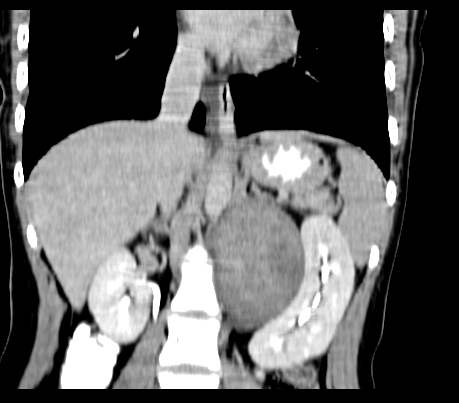

腹部平扫

动脉期

静脉期

延时5分钟

延时10分钟

重建